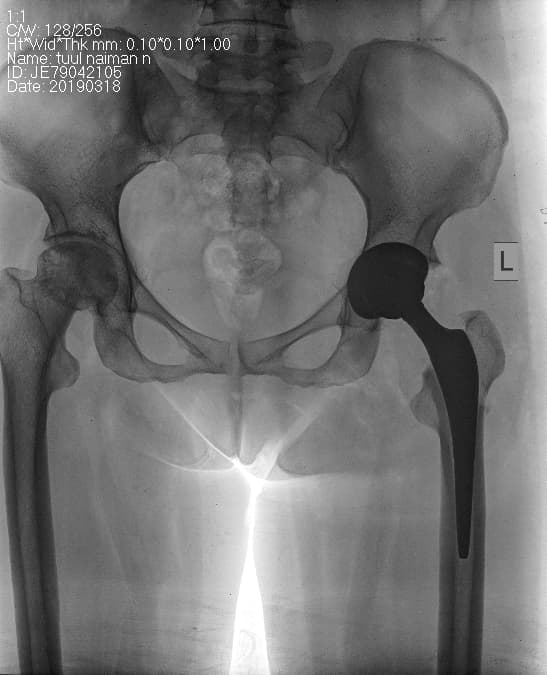

Түнхний толгой хэсгийн цусан хангамжийн алдагдалын улмаас үхжилт өөрчлөлттэй өвчтөний мэс заслын өмнөх болон дараах рентген зураг

Түнхний үе бүтэн солих мэс засал (THA) image1Түнхний үе бүтэн солих мэс засал (THA) image2